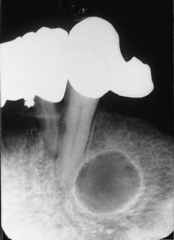

radicular cyst

-asymptomatic radiolucency associated with the root of a NONVITAL tooth